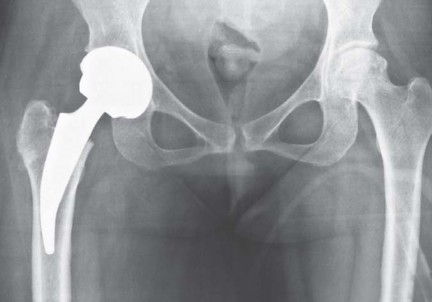

مفصل الفخذ الصناعي قصير الجذع METHA هو حل جراحي متقدم لاستبدال مفصل الفخذ، مصمم خصيصًا للحفاظ على أكبر قدر ممكن من العظم والأنسجة الرخوة في المرضى الأصغر سنًا والنشطين. يقدم هذا الجذع القصير تثبيتًا فسيولوجيًا ويقلل من آلام الفخذ، مما يتيح تعافيًا أسرع ووظيفة أفضل للمفصل.

METHA هو جذع قصير معياري يعتمد على مفصل Mayo الناجح للغاية. يجمع الزرع بين ثلاث ميزات مهمة: البناء المعياري، والتثبيت الميتافيزي، والتحميل القريب مع الحد الأدنى من حجم الجذع والطلاء المحيطي، مما يؤدي إلى تثبيت بيولوجي. ويحتوي على جميع الميزات المطلوبة من زرع فخذ حديث، وهي: الحفاظ على العظم، والتحميل الفسيولوجي لعنق الفخذ وميتافيزال الفخذ القريب، والقدرة على استعادة ميكانيكا مفصل الفخذ دون إطالة الطرف، وإمكانية الوصول الجراحي الأقل توغلاً.

تصميم مفصل METHA

يُعد METHA جذعًا معياريًا، يُثبت في الميتافيزال، وغير إسمنتي. يتميز بتصميم مستوحى من مفصل Mayo الناجح، ولكنه يتفوق عليه في عدة جوانب:

- شكل شبه منحرف واسع: يوفر ثباتًا أوليًا ممتازًا مع الحفاظ على العظم الإسفنجي.

- مادة الصنع والطلاء: يتكون من جذع مخروطي مزدوج من التيتانيوم، مغطى بالكامل بطلاء التيتانيوم النقي المسامي الدقيق (بلازمابور) مع طبقة رقيقة من فوسفات الكالسيوم ثنائي الهيدرات. هذا الطلاء يعزز التوصيل العظمي ويؤدي إلى اندماج عظمي مبكر، مما يوفر ثباتًا ثانويًا.

- الطرف البعيد غير المطلي: يعمل كدليل للزرعة على طول القشرة الظهرية الجانبية، مما يعزز الثبات الأولي العالي. لا يشارك طرف الجذع بشكل كبير في نقل الحمل، بل يعزز الثبات المحوري.

- وحدات الرأس والعنق المعيارية: تتوفر تسعة محولات للعنق مصنوعة من الكوبالت والكروم، بزوايا عنق الفخذ 130، 135، 140 درجة، وزوايا دوران 0، 7.5 درجة أمامية، و7.5 درجة خلفية لكل زاوية. تتوفر الجذوع بسبعة أحجام من 0 إلى 6. تسمح هذه المحولات المعيارية بتحسين ميكانيكا مفصل الفخذ لكل مريض على حدة دون إطالة الطرف.